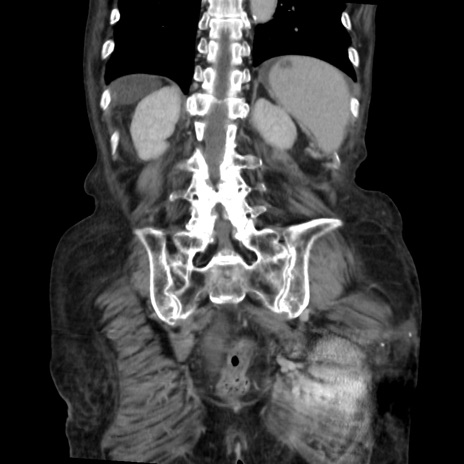

症例31(冠状断像)

【症例】80歳代 女性

【主訴】腹部膨満感

【現病歴】他院にて肝硬変にてフォロー中。1週間前から便秘、腹部膨満感、臍部腫瘤あり受診となる。

【既往歴】肝硬変

【身体所見】腹部膨隆あり、皮膚変化なし、疼痛なし。

【データ】WBC 4600、CRP 0.25